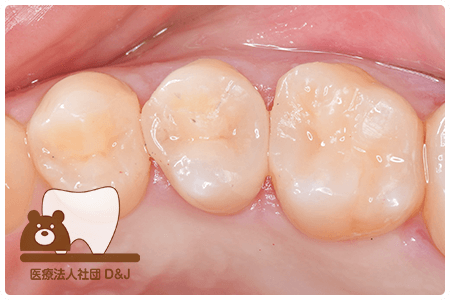

症例3フリジルコニアクラウン 左上6

治療前

治療後

59歳 男性

- 治療内容

- 虫歯で大きく失われた歯に対して、土台としてファイバーコアを使用し、その上にフルジルコニア製の被せ物を装着しました。見た目と強度を両立した自由診療の治療です。

- 治療期間

- 根の治療含めて3カ月半

- 費用

- 自費

フリジルコニアクラウン:77,000円(税込)

(R8.2月時点)

- その他の治療の費用は含まれておりません。

- リスク・副作用

- 強い力が加わると割れる可能性があります。また、噛み合わせや歯ぎしりの影響で脱離することがあります。